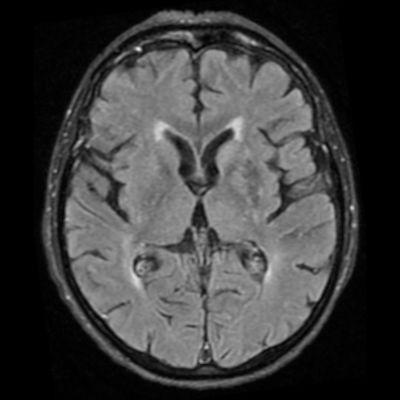

75 yaş, K

Sağ üst kolda atım şeklinde hareket

Tanınız nedir?

Nonketotik hiperglisemik hemikore

Diyabetik striatopati

Non-ketotik hiperglisemiye bağlı hemikore-hemibalizm

non-ketotic hyperglycemic hemichorea